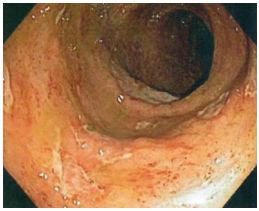

65. 28歲女性因8週的下腹絞痛合併腹瀉病史,接受進一步評估,她每天排便6至10次,其中有一至二次在半 夜,大便特徵為loose to watery with intermittent blood streaking。另外她有噁心及食慾變差現象,但無嘔 吐、發燒,也無服用藥物病史。身體檢查:體溫:37.8℃,血壓100/54 mmHg、脈搏96/min,腹部呈 現diffuse tenderness但無rigidity, guarding或rebound pain。大腸鏡檢查在升結腸、橫結腸及降結腸有如 附圖之發炎病灶,但是terminal ileum及rectum並無發炎現象,下列何者為最可能之診斷?

(A) Collagenous colitis (B) Crohn colitis (C) Ischemic colitis (D) Ulcerative colitis (E) Tuberculous colitis